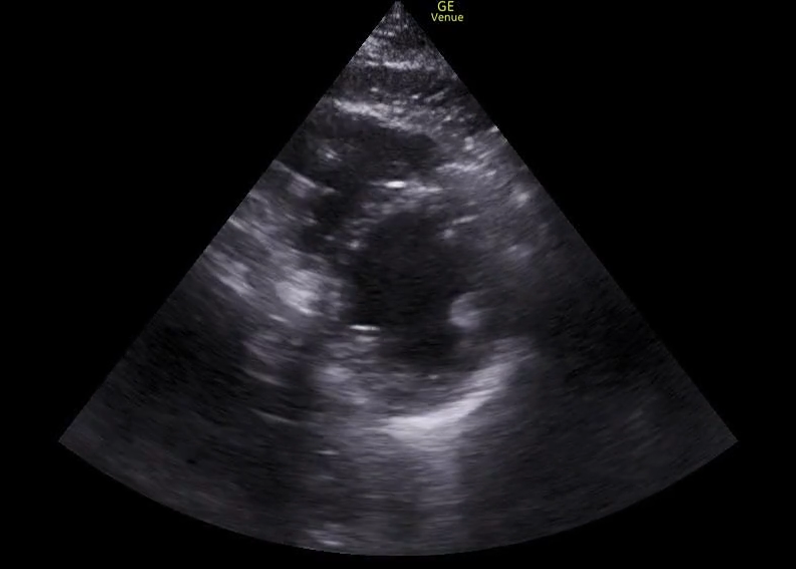

The following images (ECG and parasternal short axis view of the heart) were obtained on our patient immediately following ROSC.

The ECG shows ST segment elevation in the anterior leads, and the ultrasound shows an akinetic segment in the distribution of the LAD. This is the regional wall motion abnormality. The image below illustrates the finding. The heart cath confirmed a total occlusion of the LAD.